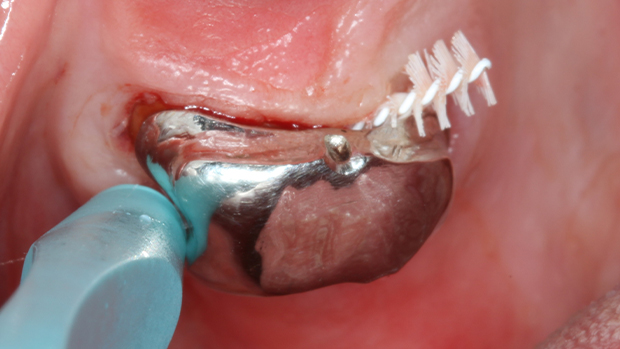

Die Basis jeder palliativen Parodontalstrategie bleibt eine kontinuierlich individuell angepasste Mundhygieneaufklärung.³ Sie muss realistisch, alltagstauglich und auf die vorhandenen Ressourcen abgestimmt sein (Abb. 2). Wenn bereits angewendete Instruktionen nicht greifen, lohnt es sich, die eigene Vorgehensweise zu hinterfragen und neu zu strukturieren.

Immer unter der Prämisse, dass keine Beschwerden bestehen, kann bei stark eingeschränkten Patientinnen und Patienten eine reduzierte, gezielt angepasste Mundhygiene nach dem Prinzip „weniger ist mehr” dazu beitragen, die Kaufunktion und damit die allgemeine Gesundheit zu erhalten (Abb. 3).